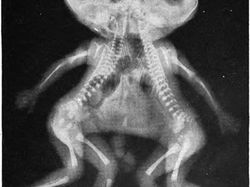

Tubuh tikus yang masih utuh di dalam perut ular. (Foto: Brightside)